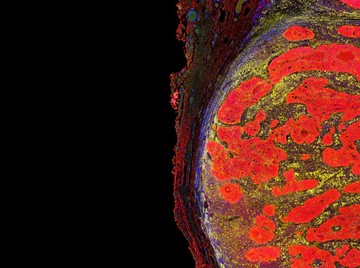

Fiziki terhelésre a „beszorított” tumorsejtek drámai változáson mennek keresztül: nem a gyors osztódásra koncentrálnak, hanem egy inváziós programot indítanak el.

Egy melanoma zebrahal-modellel dolgozva White, Hunter és munkatársaik azt figyelték meg, hogy a „beszorított” tumorsejtek drámai változáson mennek keresztül. Nem a gyors osztódásra koncentrálnak, hanem egy inváziós programot indítanak el, amely felkészíti őket a környező szövetek közötti vándorlásra.

Ennek központi szereplője a HMGB2 nevű fehérje, amely képes meghajlítani a DNS-t, és újraszervezni annak csomagolását. Amikor a sejtek nyomás alá kerülnek, a HMGB2 aktívan átrendezi a kromatin szerkezetét, hozzáférhetővé téve azokat a genomrégiókat, amelyek az invázióhoz és a gyógyszerrezisztenciához kapcsolódnak. Így a sejtek ugyan kevésbé szaporodnak, de sokkal nehezebben pusztíthatók el.

A kutatás egy másik meglepő jelenségre is rávilágított. A melanomasejtek úgy védekeznek a fizikai nyomással szemben, hogy átalakítják belső vázukat, és egy ketrecszerű szerkezetet hoznak létre a sejtmag körül. Ebben kulcsszerepet játszik a LINC komplex, amely molekuláris hídként kapcsolja össze a sejtvázat a sejtmag burkával. Ez a páncélzat megóvja a sejtmagot a sérülésektől és a DNS károsodásától, lehetővé téve a sejt számára, hogy túlélje a szoros környezet adta stresszt.